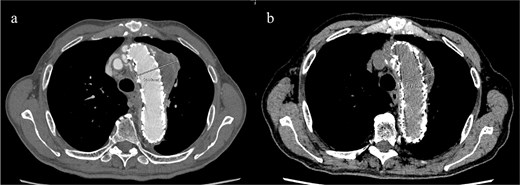

Given the ongoing hemoptysis, presumed aneurysmal expansion due to an occult endoleak, and the absence of any other obvious causes of hemoptysis, we determined that intervention for the aneurysm was necessary. TEVAR was performed using a right femoral artery approach. Initial angiography did not reveal contrast leakage into the sac (Fig. 3a). A 34 × 34 × 200 mm Gore Conformable TAG stent graft (W.L. Gore & Associates, Flagstaff, AZ, USA) was deployed to cover the distal edge of the FET. The second stent graft, a 34 × 34 × 150 mm Gore Conformable TAG stent graft, was deployed overlapping the first graft immediately after the left subclavian artery branch to cover the entire length of the FET (Fig. 3b). Considering the proximal migration, a type Ib endoleak was deemed the most likely cause. However, the possibility of a type III endoleak from the graft was also considered, so the stent graft was deployed to cover the entire area. The patient’s hemoptysis resolved completely postoperatively. A follow-up CT 2 years later showed a reduction in the aneurysm size from 56 to 44 mm (Fig. 4).

(a) Angiography performed from within the FET before deploying the stent graft showing no evidence of endoleak or aortobronchial fistula. (b) Angiography after stent graft placement. The bidirectional arrow shows the original extent of the FET insertion.